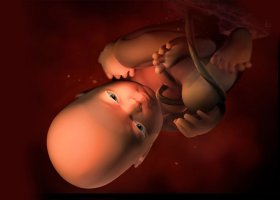

Ріст і розвиток плода

На 32 тижні довжина тіла плода досягає 42 см, а вага складає близько 1800 грамів. Маса тіла деяких здорованів досягає до цього часу двох кілограмів. У наступні тижні зазначені показники в значній мірі залежатимуть від генетичної схильності малюка. Якщо мама і тато дитини - рослі і міцні люди, то немовля до моменту народження може досягти ваги 4,5 кг і навіть більше, якщо ж батьки худорляві і невисокого зросту, то їх спадкоємець може важити, наприклад, 2,7 кг, і для нього це буде нормою.

В організмі плода на 32 тижні відбуваються нові зміни:

- голова малюка стає більш пропорційною щодо розмірів його тіла,

- становище дитини в матці стає більш статичним, тобто нерухомим. Як правило, це головне передлежання (верхівкою вниз). Згодом малюк вже не зможе змінити його аж до самого народження. Втім, деякі фахівці вважають, що на 32-му тижні ще можна допомогти майбутній мамі і малюкові, тому пропонують скористатися спеціальними методами для виправлення становища. Слід з обережністю ставитися лише до рекомендацій подружок і інших малокомпетентних людей, адже тільки лікар, який спостерігає за вагітністю, може оцінити всю ступінь ризику будь-яких зовнішніх впливів,

- на обличчі розгладжуються складки і зморшки, шкіра стає більш гладкою. На стан шкіри помітно впливає процес накопичення підшкірного жиру,

- сердечко плода практично сформовано. На даному етапі в ньому поки є отвір між лівим і правим передсердям, яке закриється відразу після появи малюка на світ,

- завдяки активізації власної імунної системи організм плоду починає виробляти антитіла, які будуть захищати його від всіляких інфекцій в перші дні і місяці після народження.

Всі органи малюка майже готові до роботи в автономному режимі, тому в разі дострокових пологів дитина є цілком життєздатним. Проте, не слід квапити хід подій: краще налаштуватися на те, що пологи пройдуть у визначений термін, адже в цьому випадку малюк народиться більше здоровим і міцним.